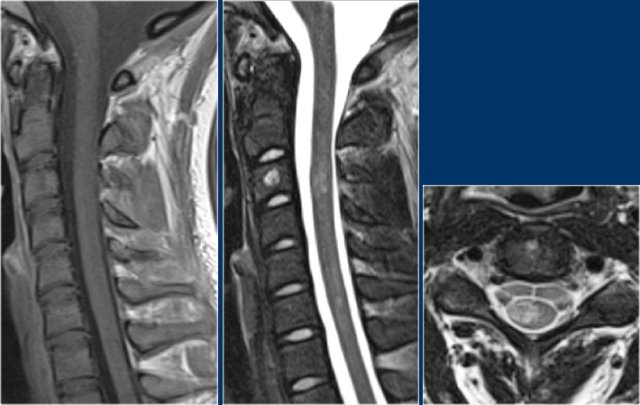

Here we have images of a typical case.

Many times the clinical history is very helpful like in this case.

This 24-year old patient had visual disturbances on one eye followed by weakness and sensory disturbances of the lower and upper extremities a couple of years later.

Now she presents with sensory disturbances of both lower extremities.

So we already think MS.

In the cord there are some well-defined lesions, but also some ill-defined foggy lesions.

The transverse image shows the dorsal location and the typical triangular shape.

Continue with the contrast-enhanced images

On the contrast-enhanced images there is no enhancement.

Active MS-lesions in the spine may enhance, but it is not that common as we see in active lesions in the brain.

Whenever spinal lesions are encountered, it can be helpful to image the brain aswell.

Now sometimes the patient is only sceduled for MRI of the spine and you don't have time to do a full brain examinations.

In those cases consider to do only a sagittal FLAIR.

Continue with the images of the brain.

The MRI of the brain shows periventricular lesions and a lesion in the corpus callosum.

These locations are very specific for MS.